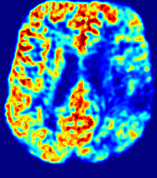

Figure 4: PIANO feature maps for another patient in the ISLES 2017 training set, where the lesion is located in the right hemisphere. Top row: segmented stroke lesion region (white) on different slices. The corresponding slices for the PIANO feature maps are shown in the following rows.

For a better insight into an estimated velocity field 𝐕𝐕{\bf{V}} and diffusion field 𝐃𝐃{\bf{D}}, we compute the following maps: (1) 𝐕rgbsubscript𝐕𝑟𝑔𝑏{\bf{V}}_{rgb}: Color-coded orientation map of 𝐕=(Vx,Vy,Vz)T𝐕superscriptsuperscript𝑉𝑥superscript𝑉𝑦superscript𝑉𝑧𝑇{\bf{V}}=(V^{x},V^{y},V^{z})^{T}, obtained by normalizing 𝐕𝐕{\bf{V}} to unit length and mapping its 3 components to red, green, blue respectively; (2) 𝐕2subscriptnorm𝐕2\|{\bf{V}}\|_{2}: 222 norm of 𝐕𝐕{\bf{V}}; (3) D𝐷D: scalar field in Eq. 5.

Fig. 3 and Fig. 4 show the PIANO feature maps estimated from two ISLES 2017 patients: all are highly consistent with the lesion in both cases. Details of the blood flow trajectories are revealed in 𝐕rgbsubscript𝐕𝑟𝑔𝑏{\bf{V}}_{rgb} by the ridged patterns and the sharp changes of colors in the unaffected (right) hemisphere, while the flat patterns appearing within the lesion provide little directional information about the velocity and indicate low velocity magnitudes. Velocity magnitudes are more directly visualized via 𝐕2subscriptnorm𝐕2\|{\bf{V}}\|_{2}, from which one can easily locate the lesion where 𝐕2subscriptnorm𝐕2\|{\bf{V}}\|_{2} is low. D𝐷D also indicates lower diffusion values in the lesion, though with less contrast potentially due to the fact that it captures the accumulated effect of CA diffusion at the voxel-level.